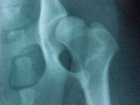

OFA MODERATE HD

Note:

1. the remodeling of the acetabulum rim

2. the flatten somewhat mushroom femoral head

3. the thicken femoral neck.